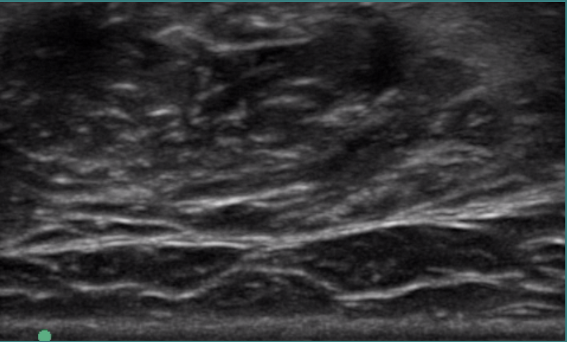

EMG for Localisation

- The importance of targeting the motor endplate has been emphasised in animal models.

- Proximity to endplate will increase the speed of uptake and degree of terminal saturation and the ultimate effectiveness of the toxin.

- Using rat anterior tibialis muscle, Shaari and Sanders demonstrated that toxin injection into the motor endplate region produces the greatest paralysis. Injections only 0.5 cm away from the region resulted in a 50% decrease in paralysis.

-

If muscle injection not near endplate BTX more likley to diffuse outside of target muscles.

Spread is estimated to be 2.5–4.5 cm, with the size of the diffusion field being proportional to the amount of toxin delivered.

Can occur across fascial planes.